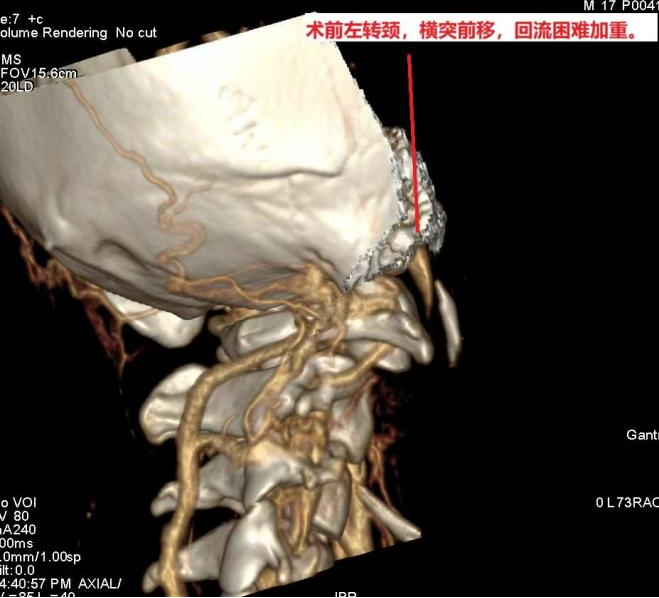

孙晓川教授团队多年来一直关注“脑鸣”及头颈部静脉系统疾病,并联合放射科李琦、陶黎团队进行了深入研究;接诊患者后,经术前详尽的影像学检查,发现其右侧颈内静脉被寰椎横突卡压,转头时血管竟完全闭塞,找到了引起患者大脑“神秘声响”的病根(图片由放射科刘传提供)。